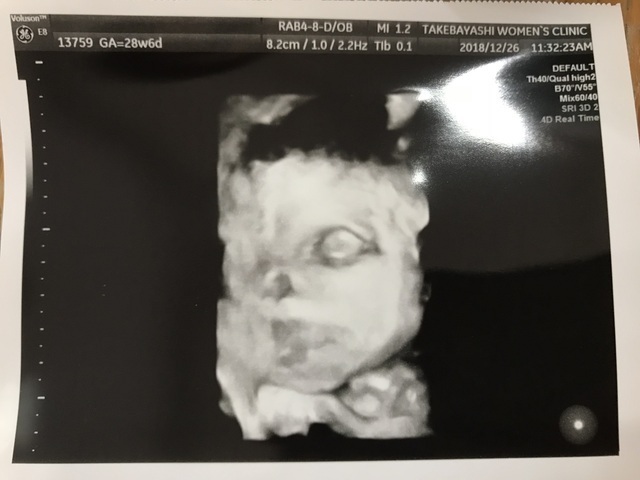

28週2日(28w2d・男の子)|yukarinnn5 さん(32歳)

エコー写真撮影時のエピソード:

検診の度に、どんな顔かな!?と思ってるのに、いつも背中側に顔を向けている息子くん。ようやく顔が見えたけど、やっぱり胎盤に一部くっついていて、これがなんとかとれたベストショット。

妊娠28週で年末を迎え…体重管理に苦労。

お医者さんに、これからケーキも餅も食べるよね!?気を付けて!と…。

年末年始を体重増やさずなんとか乗り越えたのに、そのあとなんの反動か!?仕事始めたら、また増加…。難しい…。